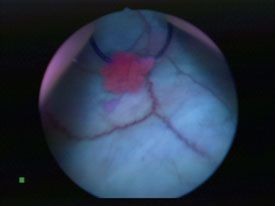

The agent, which contains hexaminolevulinate hydrochloride, is injected into the bladder through a catheter. It enters the bladder mucosa, where it accumulates preferentially in malignant cells. When illuminated with blue light from the cystoscope, the diseased cells emit red fluorescence, improving the clinician’s ability to see potentially troublesome growths.

Tumor area near resection tool shown with white light cystoscopy, top, compared with red fluorescence of Cysview, center and bottom.